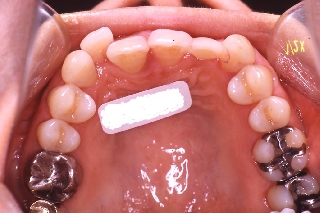

インプラント治療の為の矯正治療症例2

初診時年齢52歳。上顎前歯部欠損部インプラント治療前の咬合改善目的に来院。

当院にて前歯部の被蓋の改善を行った。

インプラント治療は専門医にて行った。

上顎 上顎 上顎